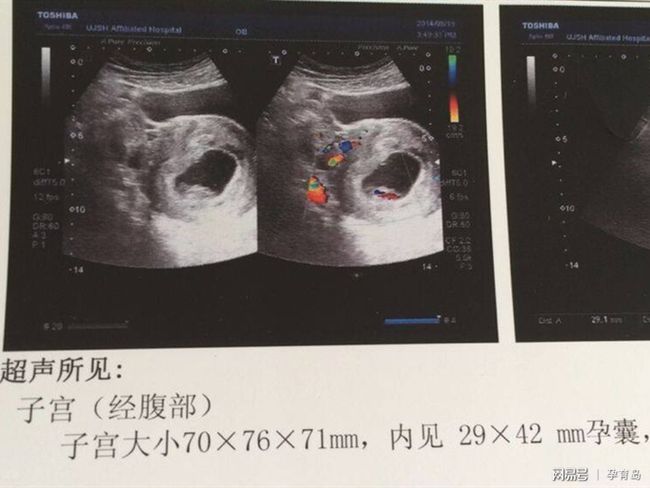

卵黃囊是胚胎發(fā)育過程中形成的一個重要結(jié)構(gòu),位于孕囊內(nèi),在胚胎的早期發(fā)育階段,卵黃囊為胎兒提供營養(yǎng)和血液供應(yīng),當(dāng)胚胎著床后,隨著妊娠的進(jìn)行,卵黃囊會逐漸消失,但在早期妊娠階段,尤其是妊娠初期,卵黃囊的存在被視為胚胎正常發(fā)育的一個重要指標(biāo)。

當(dāng)醫(yī)生通過超聲檢查觀察到卵黃囊的存在時,通常意味著胚胎已經(jīng)著床并成功建立血液循環(huán)?!坝新腰S囊基本就穩(wěn)了”這一說法是有一定道理的,這并不意味著可以完全放松警惕,早期妊娠的穩(wěn)定性還需要結(jié)合其他指標(biāo)進(jìn)行綜合評估。

1、孕囊大小與形態(tài):通過超聲檢查觀察孕囊的大小和形態(tài),可以判斷胚胎的發(fā)育情況,正常的孕囊大小與形態(tài)有助于保證胚胎的正常發(fā)育。